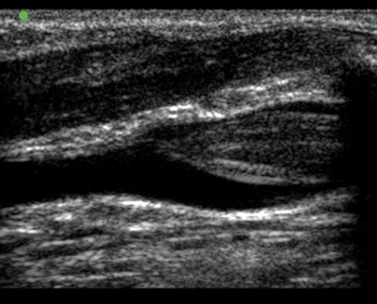

Imagen 2 de un trombo en la vena basílica con vía intravenosa periférica (IVP)